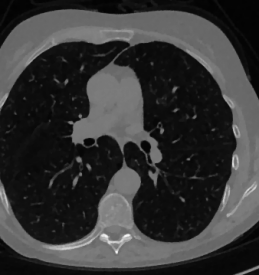

We now consider the CT protocol whose results are reported in Figure 6.

In this case, the tomographic reconstruction is more challenging than in the previous experiment. The starting image has evident streaking artifacts and blur and some details are lost, especially in the first zoom. The artifacts are reduced in the (top right image), where some details are recovered and the edges are quite neat.

The image obtained with the proposed RISING (bottom right) is visually an excellent reconstruction. It is very similar to the image, whose training, we remark, is based on more informative target images.

In Figure 7 we plot for these experiments, the same profiles of Figure 5.

In the left graph, we analyse the performance of LPP approach: the reconstruction gets values quite close to the GT, but it does not fit well the target black line.

In the right graph, we analyse the performance of RISING approach: the solution almost overlaps the target profile, confirming that the network has correctly learned.

At last we underline that the solutions of the CS regularized model are very similar in case of and geometries.